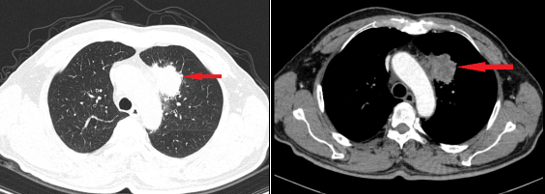

Qua thăm khám và chụp CT lồng ngực, bác sĩ phát hiện nam bệnh nhân có khối u ở thùy trên phổi trái, được xác định là ung thư biểu mô tuyến phổi giai đoạn muộn. Nội soi đại tràng tiếp tục phát hiện một khối loét, kết quả sinh thiết cho thấy ung thư biểu mô tuyến đại tràng giai đoạn sớm, thuộc dạng kém biệt hóa (tế bào ung thư phát triển nhanh, khó kiểm soát). Các xét nghiệm CT ổ bụng, MRI sọ não và siêu âm hạch cổ chưa ghi nhận di căn.

Khối u tại phổi của bệnh nhân. Ảnh: TTCC.